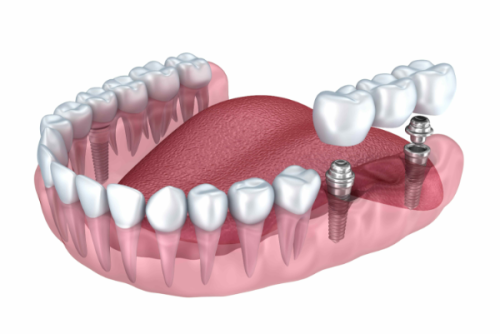

杭州英博口腔在种植牙技术方面实力超群。首先是即刻负重技术,医院累计完成半口/全口种植超1200例,丰富的临床经验让医生们能够熟练运用这项技术,为患者快速修复牙齿功能。对于单颗瑞士ITI种植牙来说,即刻负重技术可以让患者在更短的时间内拥有正常使用的牙齿,大大减少了等待时间。

再者,医院采用的数字化种植技术误差率 < 0.1mm,可避免神经血管损伤。在进行单颗瑞士ITI种植牙手术时,精细的操作至关重要。数字化种植技术能够让医生更正确地规划种植位置和角度,确保种植体的稳定性和安心性,为患者带来更好的种植成效。